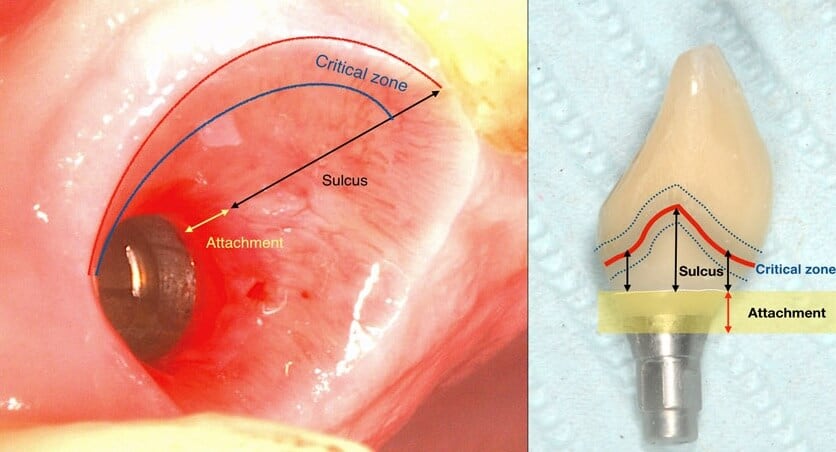

A deep sulcus in the interproximal area of anterior implants is the result of the need for natural lookiong aesthetics and paillae.

applied at baseline, peri implant tissues with both deep and shallow sulcus remained equally free of inflammation. It is well established since the time of Badersten and Egelberg in the 80’s and 90’s that patient applied oral hygiene will reach no deeper than 0.5-1mm in the sulcus. Yet this was always enough to prevent disease or maintain the outcomes of treatment. So this is where our true battlefield lies: not at the bottom, but at the top of the sulcus, where the prosthesis meets the peri-implant tissues. Disturb the biofilm formation right there, and there will be nothing left to cause inflammation or move apically. Let it accumulate and mature and within a couple of weeks mucositis will be established with the biofilm expanding in all directions, including deeper in the sulcus.

It’s not just the Biofilm, it’s the Emergence Profile!

And this is where we reach the “bottom line” of our investigation: What is the single most likely reason for preventing the biofilm from being removed? You guess right: It’s the prosthesis! And actually, not the entire prosthesis, but this critical circumferential couple of mm that we call “emergence profile”. A study in Sweden by Serino et al, found that the prosthesis was blocking the access to oral hygiene in 48% of the patients diagnosed with peri-implantitis. In my experience with such cases, modification of the prosthesis is an essential step before any attempt to decontaminate the implant. What really strikes me though, is that none of the major published studies I have come across so far in the treatment of peri-implantitis actually mentions anything about prosthesis modification in their protocol. Yet it is essential: Treatment of peri-implantitis begins at the prosthesis.

A proper emergence profile is the one that allows direct access to the top of the sulcus and the “danger zone” all around the prosthesis. On the contrary, a typical prosthesis design that blocks access to the sulcus is the “ridge lap”. A ridge lap is a horizontal extension of the prosthesis starting from the top of the sulcus and “riding” the alveolar ridge in mesiodistal or palatolingual direction. We commonly assess the emergence profile in the mesio-distal direction (probably because this is what radiographs show us), but ridge lap is very common (and thus damaging) in the bucco-palatal dimension, too. A recent study by Katafuchi et al, actually showed how the concavity of the emergence profile is important (with concave profile better to convex) and with an emergence angle of more than 30 degrees being significantly correlated with peri-implantitis.